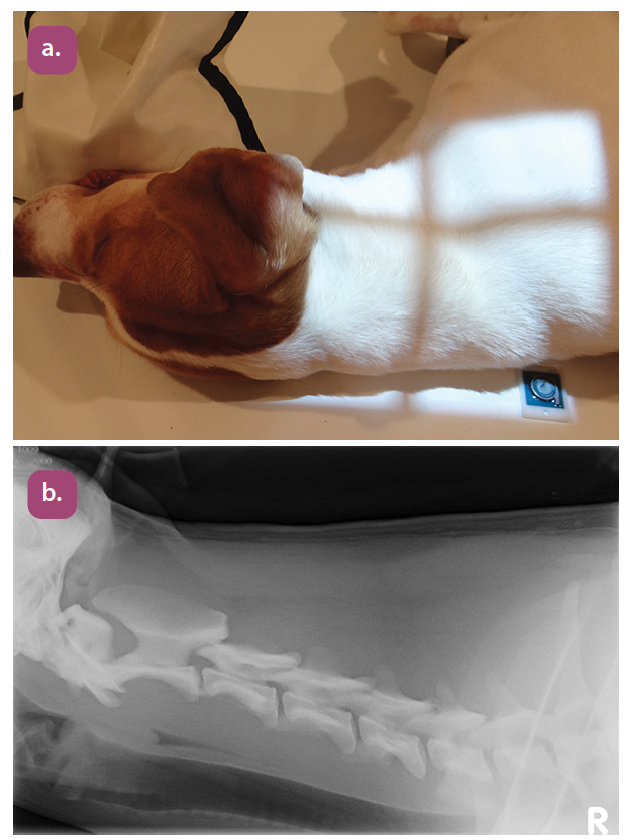

lateral cervical spine flexed projection